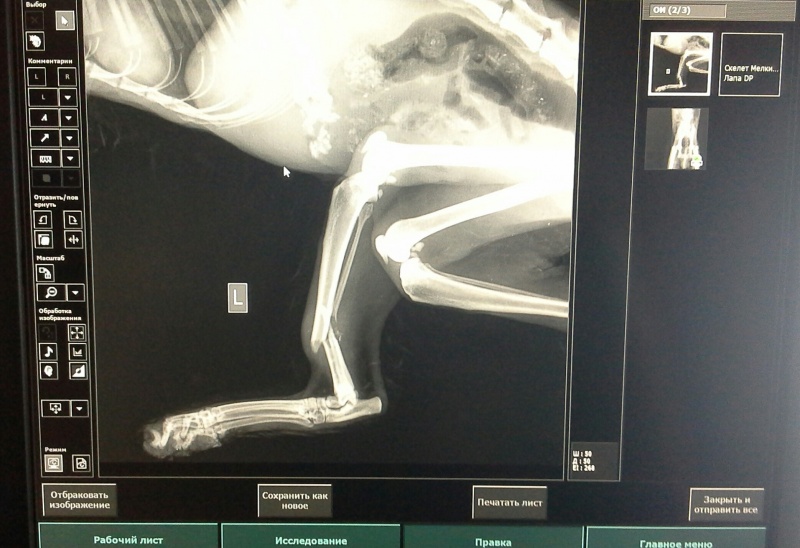

Очень тяжело... Мне казалось, что все складывается самым удачным образом. Нам удалось среди ночи попасть на прием именно к Олегу Анатольевичу. Котика очень внимательно осмотрели. На рентгене был обнаружен перелом задней лапки. Сутки котика должны были понаблюдать и если все хорошо, то на вторник была назначена операция. Я оставила котика и уехала с легким сердцем и с полной уверенностью, что все у него теперь будет хорошо. Как же жаль малыша :cray-1: :cray-1: :cray-1:

Не знаю зачем, но прикрепляю фотографии, которые собиралась выложить в теме.